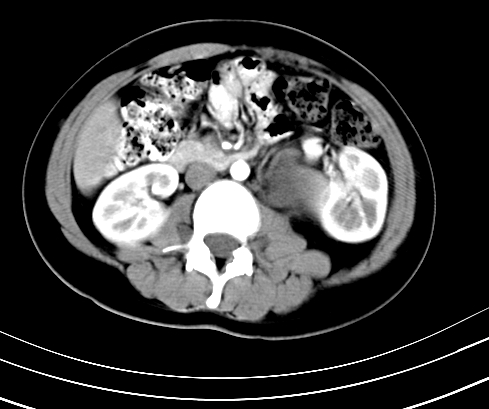

腹部平扫

动脉期

静脉期

延时5分钟

延时10分钟